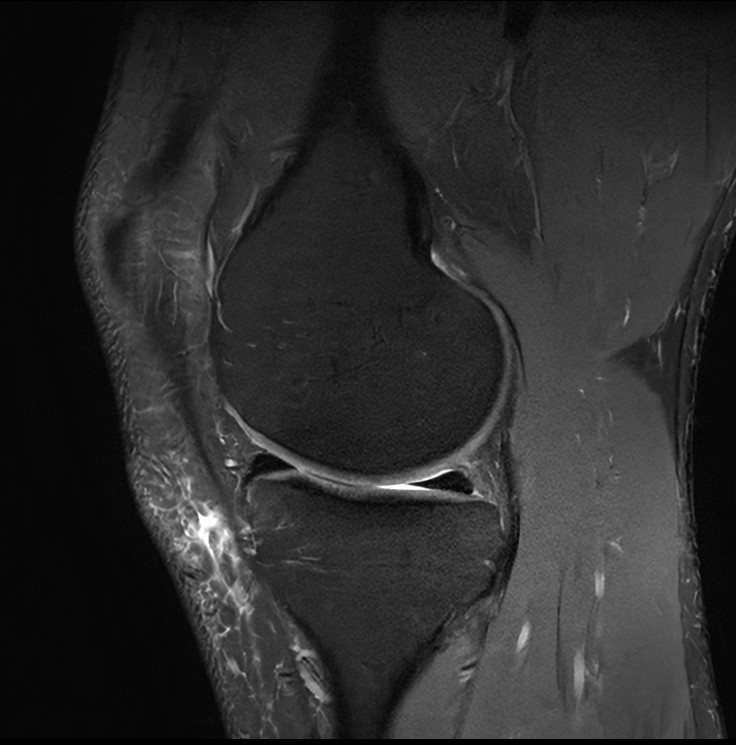

Fast Knee imaging with SmartSpeed Precise